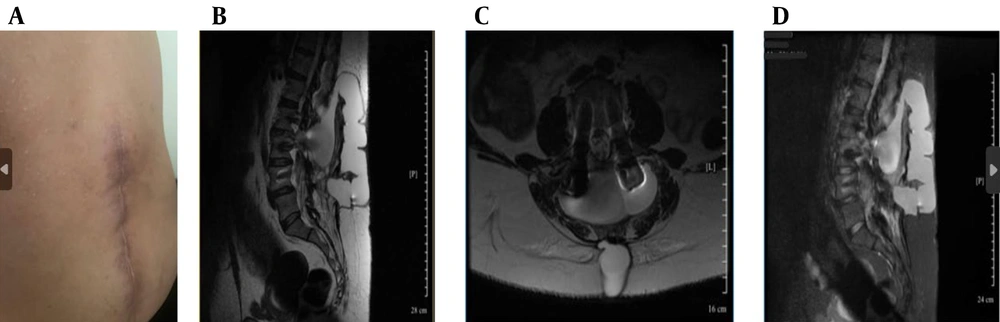

Despite repair, CSF leakage and orthostatic headaches persisted (Figure 1A).

Clinical and magnetic resonance imaging (MRI) findings (A - D): A, postoperative lumbar scar with signs of cerebrospinal fluid (CSF) leak; B, sagittal T2-weighted MRI showing posterior epidural CSF collection; C, axial T2-weighted MRI showing hyperintense fluid posterior to the thecal sac; D, sagittal short tau inversion recovery (STIR) MRI showing cranially extending epidural CSF leak.

Ongoing symptoms prompted further evaluation. The CT myelography was unavailable, so magnetic resonance (MR) myelography was used instead, revealing an active CSF leak at L4-L5 (Figure 1B - D and 2A), confirmed by contrast extravasation (Figure 2B and C). Given the failure of surgery and conservative therapy, an EBP was indicated. Direct lumbar access was avoided for three main reasons: (1) Postoperative fibrosis and adhesions at L4-L5, (2) risk of cephalad migration reducing efficacy, and (3) procedural difficulty associated with reoperated anatomy. A caudal approach was chosen for broader epidural spread, avoidance of manipulation of the surgical site, and minimizing procedural risks. Informed written consent was obtained from the patient for both the medical procedure and publication of this case report, in accordance with the Declaration of Helsinki. Ethical approval for this work was granted by the Research Ethics Committee of Tehran University of Medical Sciences (IR.TUMS.IKHC.REC.1404.152).